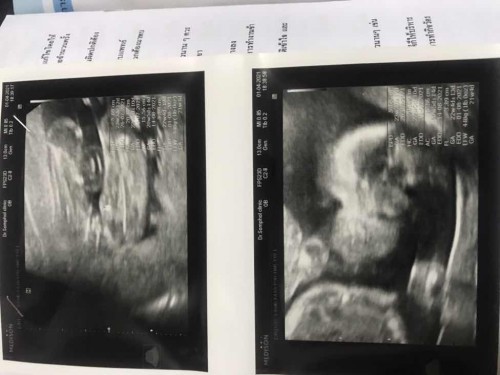

20week ตั้ง ครรภ์

น้องหญิงหรือชายคะ

หญิงค่ะแม่...ไม่มีอะรัยโด่เลยค่ะ

หญิงนะคะแม่